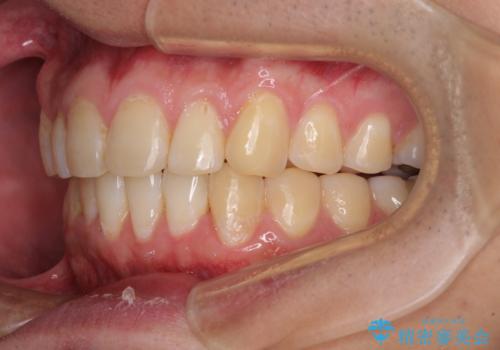

- 上下前歯のデコボコを気にして来院された患者様です。

前歯のデコボコ以外に左側の奥歯の咬み合わせに問題がありましたが、価格を抑え、短期間で気になる前歯を治したいとのことでした。

写真より左側臼歯の咬合がタイトではないことが分かりますが、こちらは保定期間に徐々に咬合させていくこととしました。